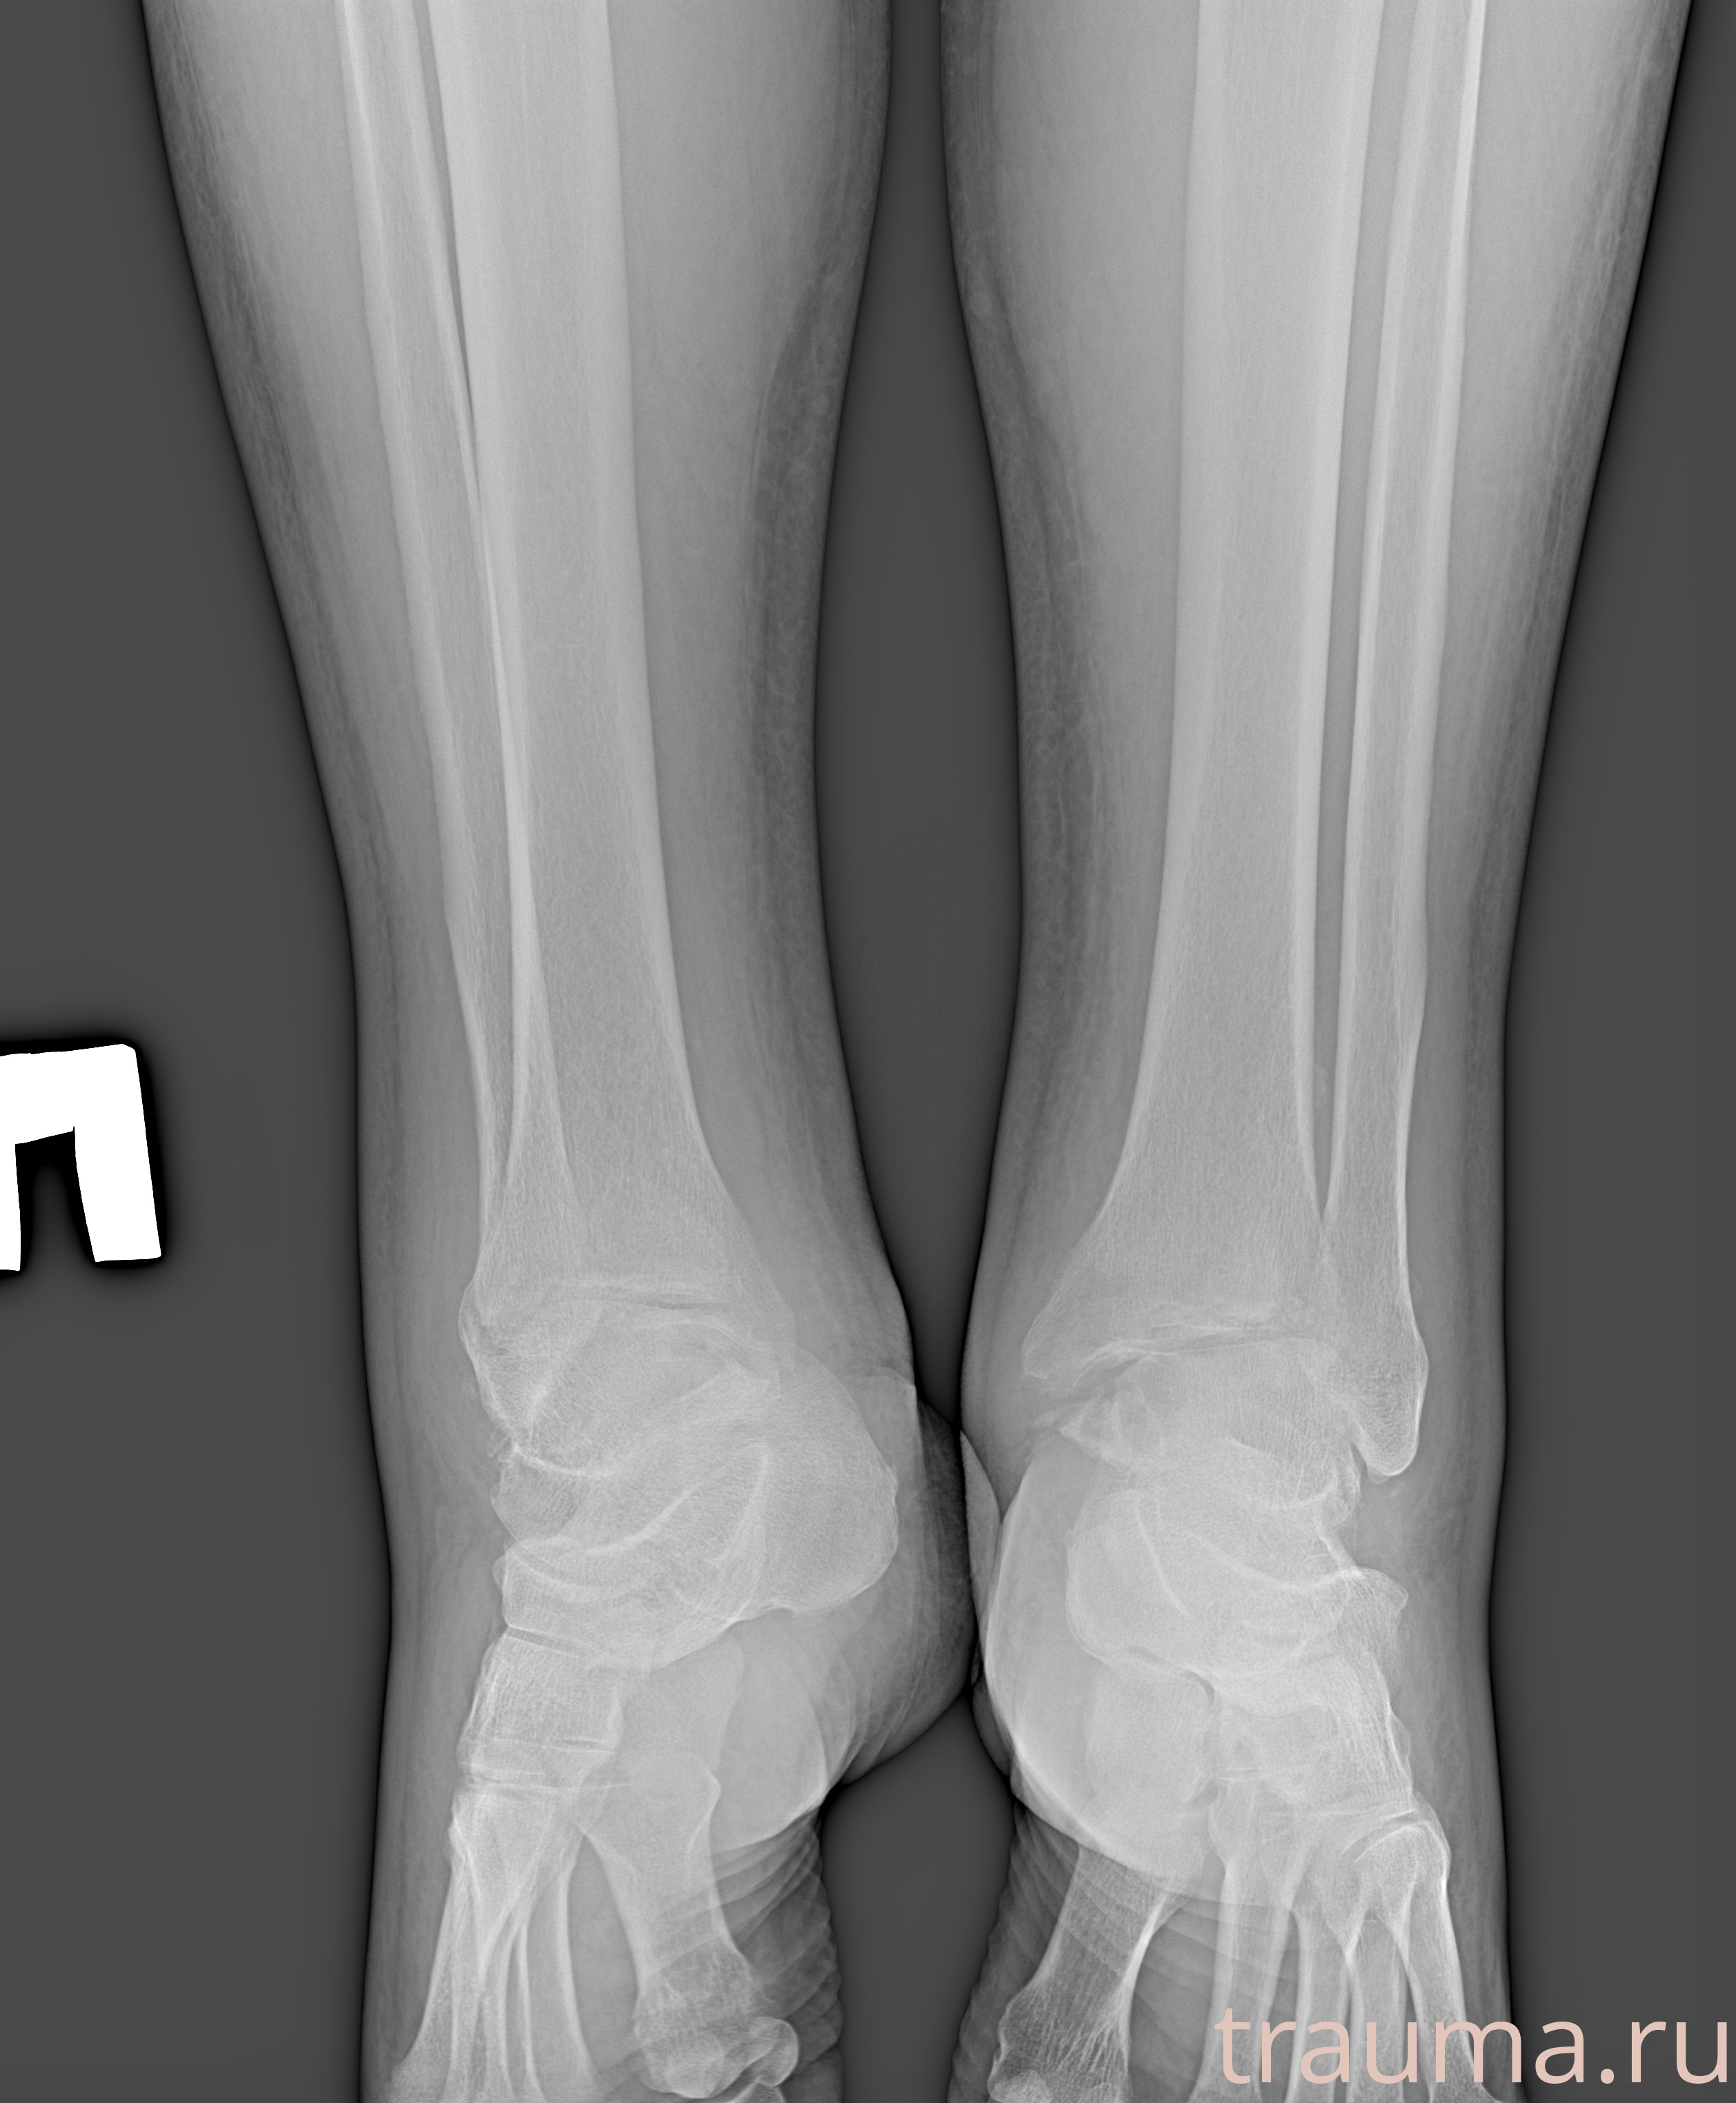

Рентгенограммы

Рентген на дому: по вашему адресу приезжает врач-рентгенолог, травматолог-ортопед с мобильным рентгеновским аппаратом, проводит диагностику травмы или заболевания, делает необходимые рентгенограммы, дает рекомендации по дальнейшему лечению. Получить качественные снимки в домашних условиях возможно благодаря уникальной методике, разработанной МосРентген Центром для института  Склифосовского